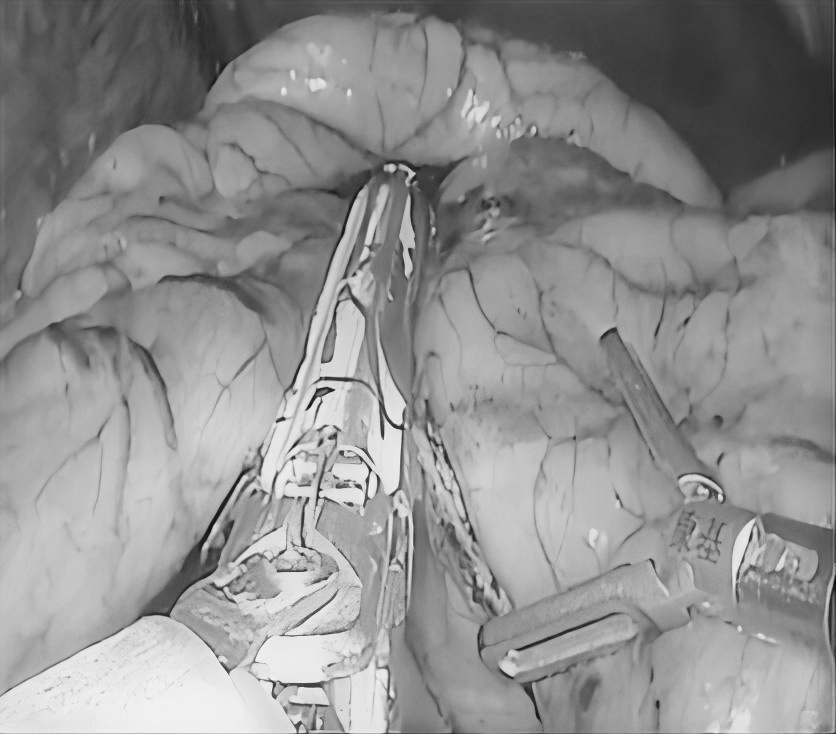

无数次立下减肥的誓言 尝试过五花八门的减肥方法 节食饿得头晕眼花 运动累得精疲力竭 但体重却像坐过山车 稍有松懈 就迅速反弹 别担心 或许减重手术 就是改变您体重的 关键契机 当前,肥胖已不仅仅是关乎外貌美观的问题,更像是一颗隐藏在身体里的定时炸弹,悄然引发各种慢性疾病。对于重度肥胖朋友来说,传统的饮食控制和运动往往收效甚微。而减重手术,为肥胖人群重获健康与自信带来了新的选择。 什么是减重手术? 减重手术,也被称为代谢手术,主要是对消化系统进行 “重塑”。目前,常见的手术方式有腹腔镜袖状胃切除术、腹腔镜胃旁路术及胃束带手术等。 比如,通过缩小胃容量,让您进食少量食物就有饱腹感,或者改变消化道结构,减少身体对营养的过度吸收。 胃旁路手术 袖状胃切除术 胃束带手术 减重手术真的有效果吗? 减重明显,告别肥胖 接受减重手术后,一般1到2年内,可以减掉超重体重的 60%-80%,让您告别肥胖困扰。 改善代谢,减少疾病 能够有效缓解Ⅱ型糖尿病、高血压、高血脂等肥胖相关疾病,让您重新拥有健康的身体状态。 减重手术,适合哪些人? 减重手术并非人人适用,需要经过严格、专业的术前评估。一般来讲,如果体重指数(BMI)≥30kg/m²,或者 体重指数(BMI)≥25 kg/m² 且合并有严重代谢性疾病,那么就可以将减重手术纳入考虑范围。 普外科专家简介 梁 跃 中共党员,普外科党支部书记、主任,主任医师 临床擅长:对普外科各类肿瘤手术具有丰富的临床经验。 毕业于遵义医学院,遵义市医学会小儿外科学分会常务委员,遵义市肛肠协会理事,遵义市医学会核医学分会(第二届)委员会委员;荣获第三期“黔医人才计划”优秀学员称号;主持市级课题1项,完成省级课题1项,在国内各类刊物上发表论文10余篇。 钱科洪 普外科副主任医师 临床擅长:从事普外科临床工作30余年,对各类普外科疾病的诊治、乳腺、甲状腺、胃十二指肠、结直肠等疾病及疑难杂症具有丰富的临床诊疗经验。 毕业于遵义医学院临床医疗系,2009年前往中山大学附属第一医院微创外科进修学习,在国内各专业期刊发表论文数篇。 贵州航天医院普外科简介 基本情况 贵州航天医院普外科成立于19世纪60年代,前身属于原航天部O61基地3417医院外一科,1998年更名为普外科,下设胃肠外科、肛肠外科2个亚专业科室,拥有专科设备和技术,是中国疝病专科联盟单位,贵州医科大学附属医院胃肠外科专科联盟单位。开放床位40张,配备医护人员21人。 专科特色 普外科致力于胃肠及肛肠疾病的外科临床诊治及科研,以腹腔镜微创外科技术为本,形成以快速康复治疗胃肿瘤、结直肠肿瘤、小肠肿瘤、直肠脱垂、肥胖病、急腹症、各类疝、痔、瘘等专科特色,同时注重胃肠疾病尤其是结直肠恶性肿瘤的基础研究和临床转化研究。 开展手术:腹腔镜下胃癌根治术,腹腔镜下袖状胃切除术,腹腔镜下胃肠道间质瘤切除术,腹腔镜下结、直肠癌根治术,胃癌、结直肠癌的精准治疗,腹腔镜下小儿疝气、成人疝修补术,腹腔镜下阑尾手术,内痔的硬化注射治疗及痔疮的微创治疗:ATH、PPH、TST,直肠脱垂的各种手术治疗,难治性伤口VSD技术,鼻胃肠管、肠梗阻导管置入术,肛肠术后间歇性导尿技术,并引进了中医适宜技术,也为各种化疗患者提供输液港安装,提高患者就医体验。 腹腔镜下腹股沟疝无张力修补术 腹腔镜下腹股沟疝 无张力修补术 腹股沟疝里金斯坦(Lichtenstein)手术 PPH微创术治疗环状混合痔 黏连性或炎性肠梗阻-肠梗阻导管 腹腔镜袖状胃切除 腹腔镜阑尾 切除术 腹腔镜阑尾肿瘤 切除术 腹腔镜下结肠癌根治术 诊疗范围 胃肿瘤、结直肠肿瘤、小肠肿瘤、肥胖症、各类急腹症、腹部外伤、腹壁疝、便秘、直肠脱垂、痔疮、肛瘘、肛裂等胃肠、肛肠外科疾病。 END